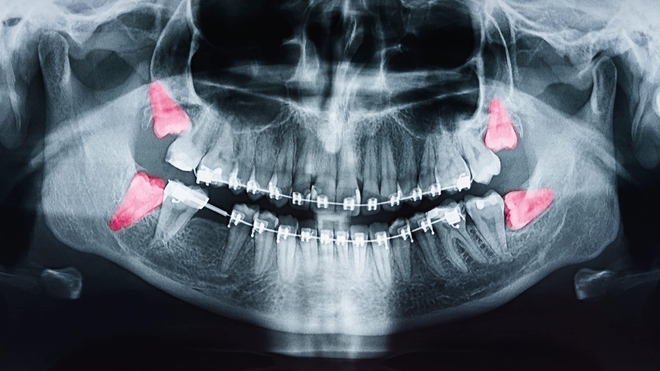

Vì mọc khi xương hàm đã cứng cáp, có niêm mạc, mô thì phủ dày bên trên nên khi răng khôn xuất hiện chúng sẽ thiếu không gian để phát triển. Cũng vì vậy mà những chiếc răng khôn thường mọc ngầm, bị lệch lạc hay đâm cả vào chiếc răng bên cạnh vì thiếu chỗ. Do đó quá trình mọc răng khôn khiến chúng ta bị đau đớn âm ỉ, khó chịu vô cùng. Những người bị nặng còn bị đau buốt, viêm nhiễm.

Trong thực tế, không phải người lớn nào cũng có răng khôn. Ước tính có khoảng 65% dân số sẽ mọc răng khôn và không phải ai cũng phải nhổ chúng đi. Chỉ các trường hợp bị răng khôn quấy nhiễu, ảnh hưởng đến hoạt động bình thường của răng miệng thì mới cần chỉ định đi nhổ răng. Hành trình nhổ răng khôn vẫn luôn là cơn ác mộng của rất nhiều người trưởng thành.

Vì sao luôn mọc ở chỗ không ai muốn, gây đau đớn nhưng răng khôn lại được đặt cái tên “thông minh” như vậy? Đáp án thật ra rất hợp lý - Ảnh 1.

Mọc răng khôn là nỗi ám ảnh của biết bao người